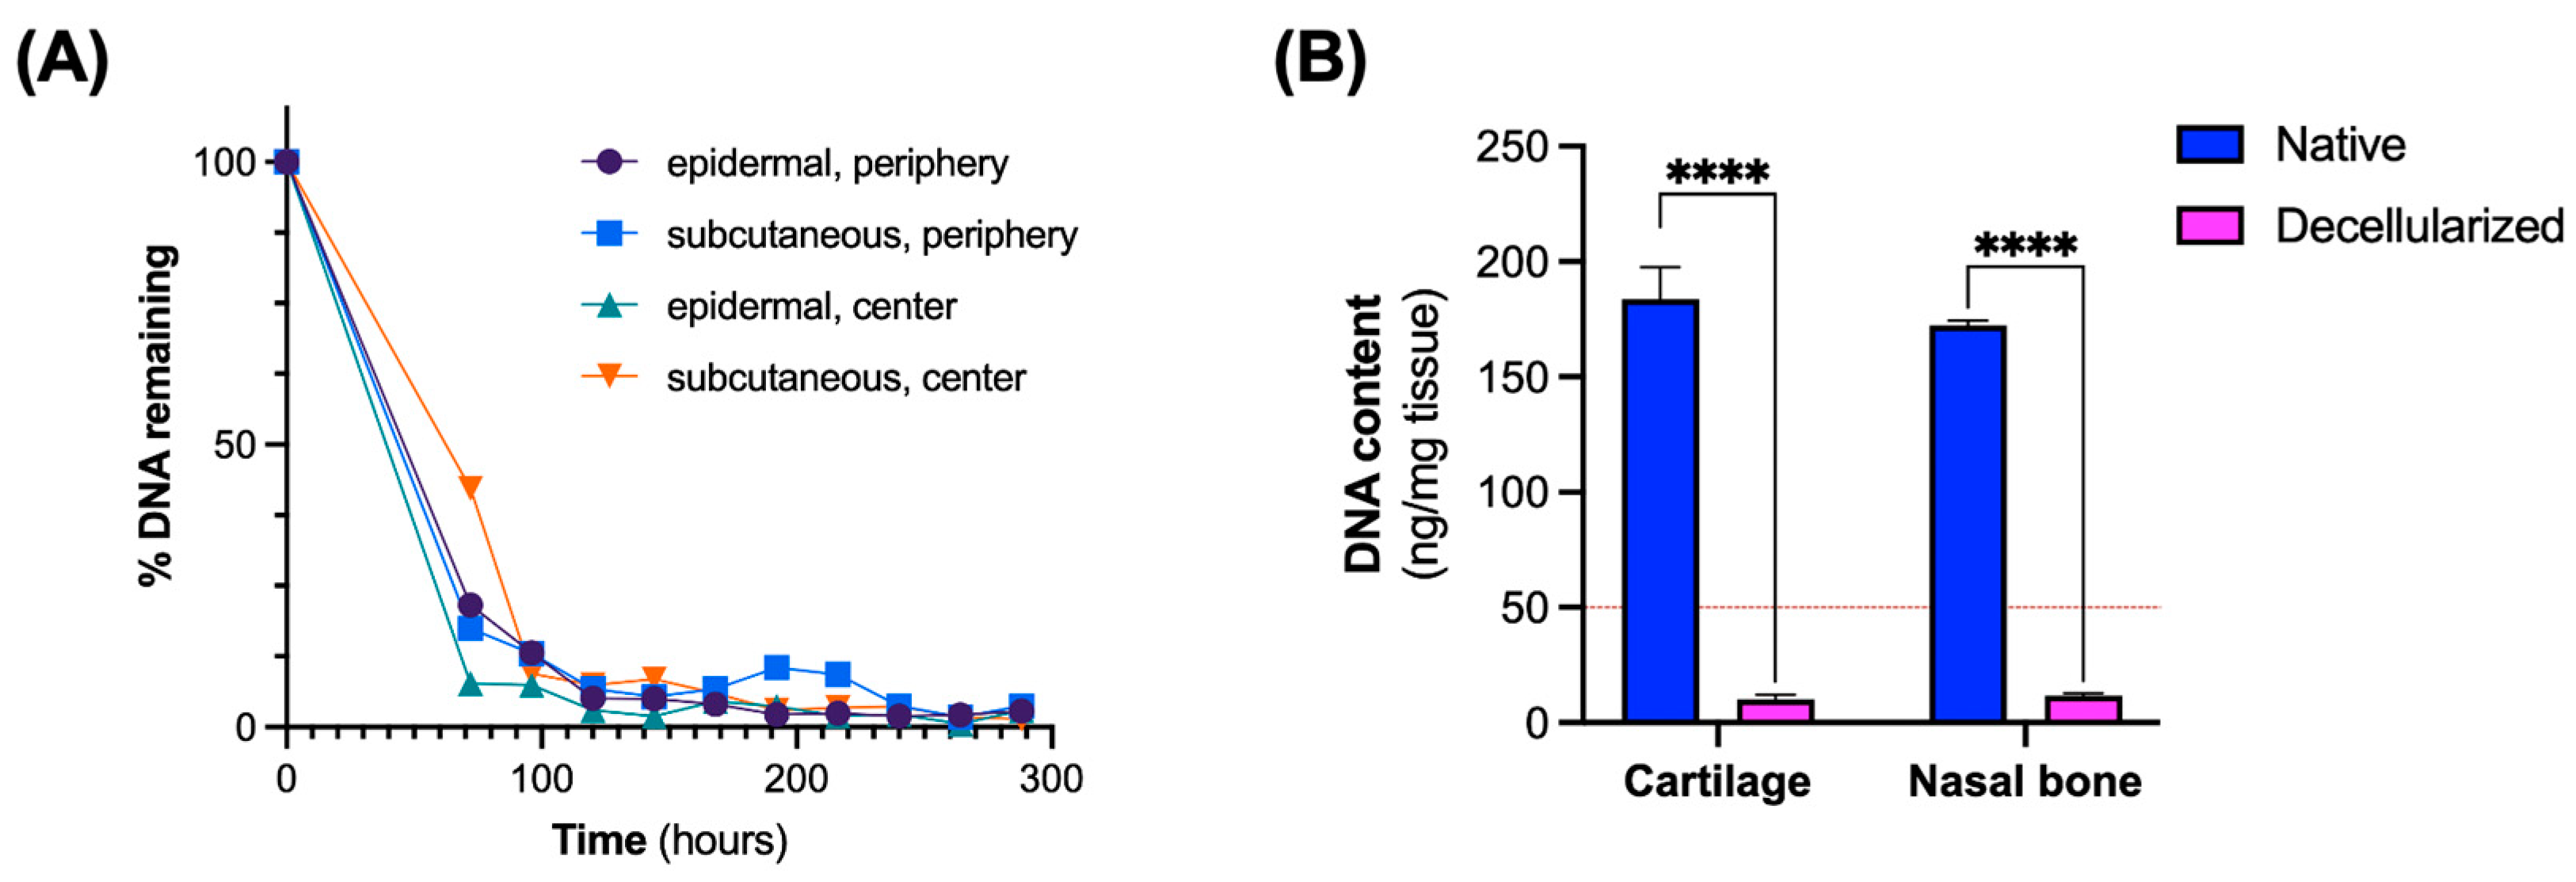

2.3. Analysis of DNA Removal

3.1. Assessment of Decellularization Efficiency